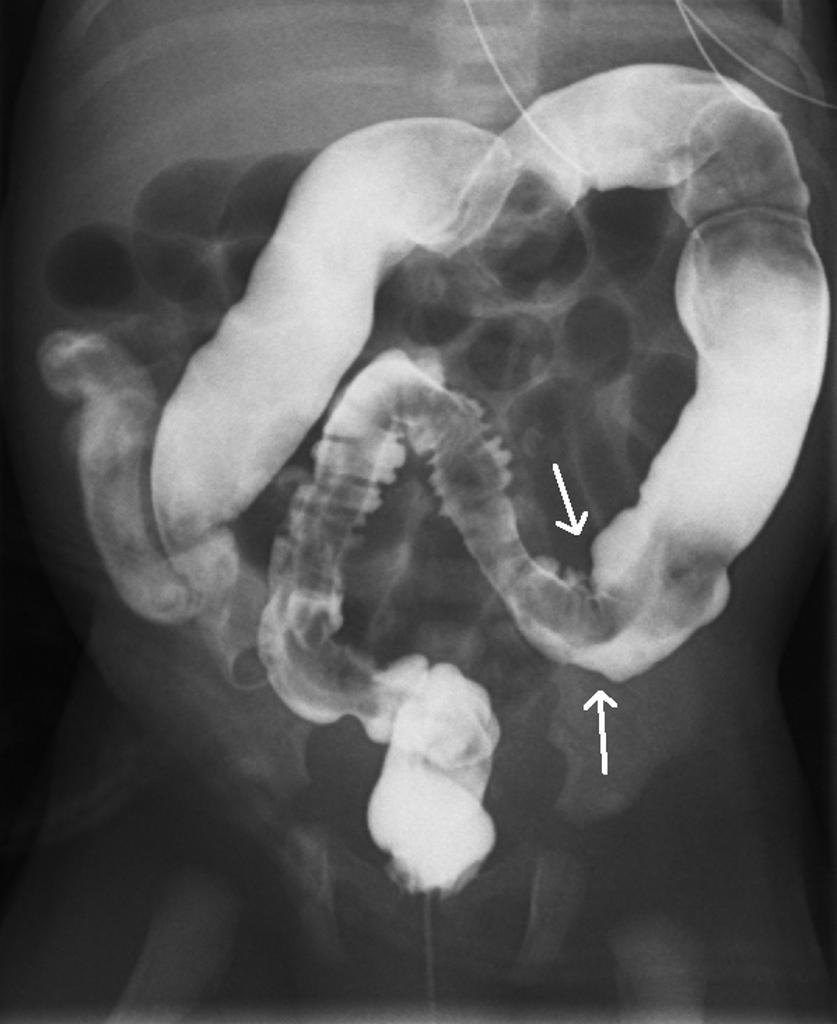

Рентгеноконтрастные Исследования Кишечника: Визуализация и Методики

Раздел: Иллюстрированный журнал